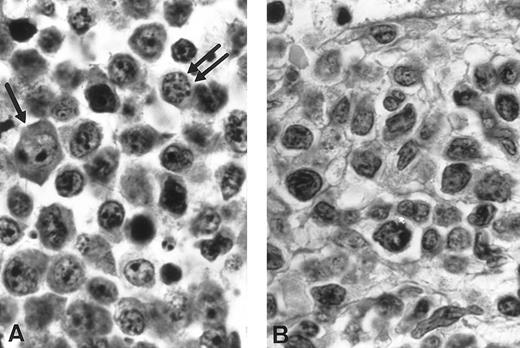

Morphological studies of pathologicals specimens. (A) Imprint of the three cases of NK-NHL. Case no. 1: Large blastic lymphoid cells looked like immunoblasts with a high mitotic rate (MGG, original magnification × 3,300). Case no. 2: Medium lymphoid cells with irregular nuclei and fine chromatin (MGG, original magnification × 3,300). Case no. 3: Medium and large lymphoid cells with vacuoles and azurophilic granules in the cytoplasm (MGG, original magnification × 3,300). (B) Immunophenotypic analysis. Coexpression study of CD3 and CD56 in the three cases found the unique tumoral phenotype CD3− CD56+. Heterogeneity is described concerning CD4 and CD8 expression. Case no. 1: CD4−CD8+; Case no. 2: CD4+CD8−; Case no. 3: CD4−CD8−.

In the first case, the imprint from a lymphadenopathy was mainly composed of large blastic lymphoid cells. The cytoplasm was abundant and slightly basophilic but without cytoplasmic granules. The nucleus was sometimes irregular with a single centrally located nucleolus. These blast cells looked like immunoblasts. Acid phosphatase polar positivity was observed in 100% of the blasts. Mitoses figures were frequent (Fig 1A). Histopathologic study of a voluminous lymph-node showed a diffuse infiltrate by medium to large cells with a basophilic cytoplasm, round nucleus containing medium and sometimes large nucleoli. Some medium-sized cells realized a plasmacytoid pattern (Fig 2A). A reappraisal of the ileal initial resection discovered similar cells infiltrating the mucosae between the glands and some in the epithelium between the cells.

Histological findings (cases no. 1 and 2). (A) Case no. 1: High-grade T-cell lymphoma, large cell predominance; proliferation of large lymphoid cells with immunoblasts (arrow) and medium-sized cells with plasmacytic differentiation (double arrow). Notice the discrete nuclear pleomorphism (hematoxylin-eosin, original magnification × 1,320). (B) Case no. 2: High grade pleomorphic T-cell lymphoma, medium-sized and large cell predominance. Proliferation of lymphoid cells with irregularly indented nuclei of various size and small nucleoli looking like a pleomorphic T-cell lymphoma with predominance of medium cells (hematoxylin-eosin, original magnification × 1,320).

In the second case, bone marrow aspiration showed an infiltrate of medium-sized lymphoid cells with fine chromatin. The blast cells contained irregular nuclei, usually with some indentations. The nucleoli were slightly apparent (Fig 1A). Acid phosphatase was negative. On bone marrow biopsy, a diffuse interstitial infiltrate with focal reinforcements was seen associated with a systematized myelofibrosis (Fig 2B). The cells were medium and large with slightly basophilic cytoplasm.

In the third case, the cervical lymph node imprints showed medium and large lymphoid cells. The nuclei exhibited a finely clumped chromatin. The basophilic cytoplasm was relatively abundant with some vacuoles and small azurophilic granules. Mitoses were frequently observed (Fig 1A). Histopathologic study of the lymph node showed a diffuse infiltrate with a starry sky pattern caused by numerous disseminated histiocytes with tingible bodies (Fig 3A). The lymphomatous cells were medium sized, with either an irregular or a more round nucleus with a basophilic cytoplasm. The lymphoma was classified as a high grade pleomorphic T-cell malignant lymphoma with large cell predominance. (Fig 3B). The bone marrow biopsy disclosed a diffuse massive infiltrate constituted by the same cells without myelofibrosis.